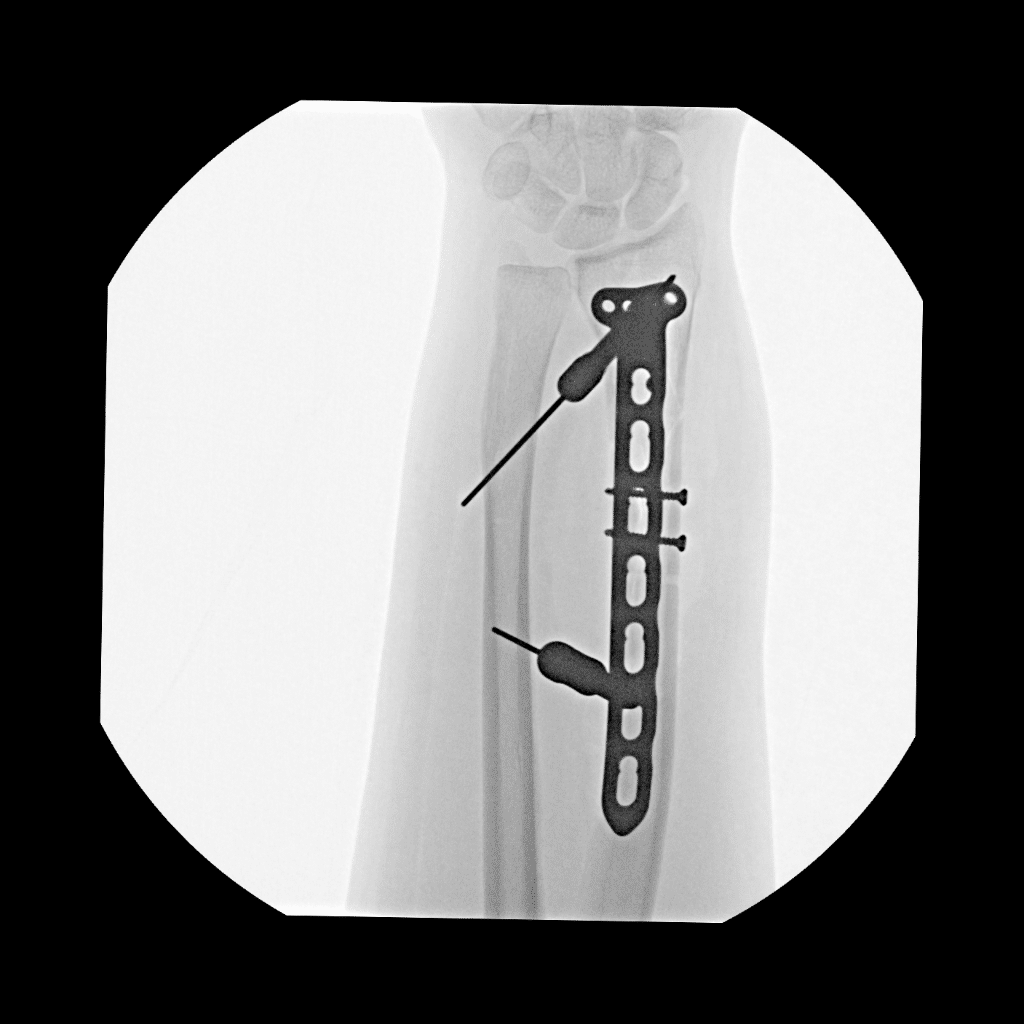

Because of the complexity of the break, orthopedic surgeons performed open reduction internal fixation (ORIF) surgery the following day. The procedure involved the placement of surgical hardware to stabilize the wrist.

• Comminuted distal radius fracture with ulnar dislocation

• Displaced fracture of the distal radius

• Significant pain and wrist deformity requiring emergency reduction under sedation